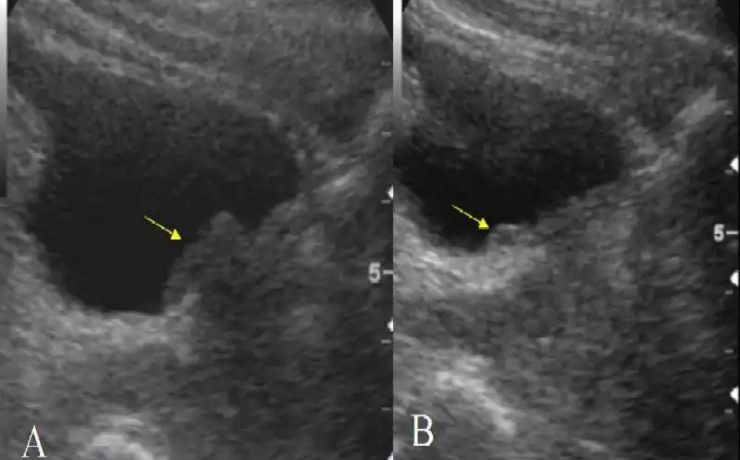

Este es un artículo de revisión publicado por el Departamento de Ginecología y Obstetricia del Hospital William Beaumont, Oaklahoma USA. La placenta accreta con sus variantes increta y percreta son una causa importante de hemorragia en el segundo y tercer trimestre de gestación representando hasta el 50% de las histerectomías